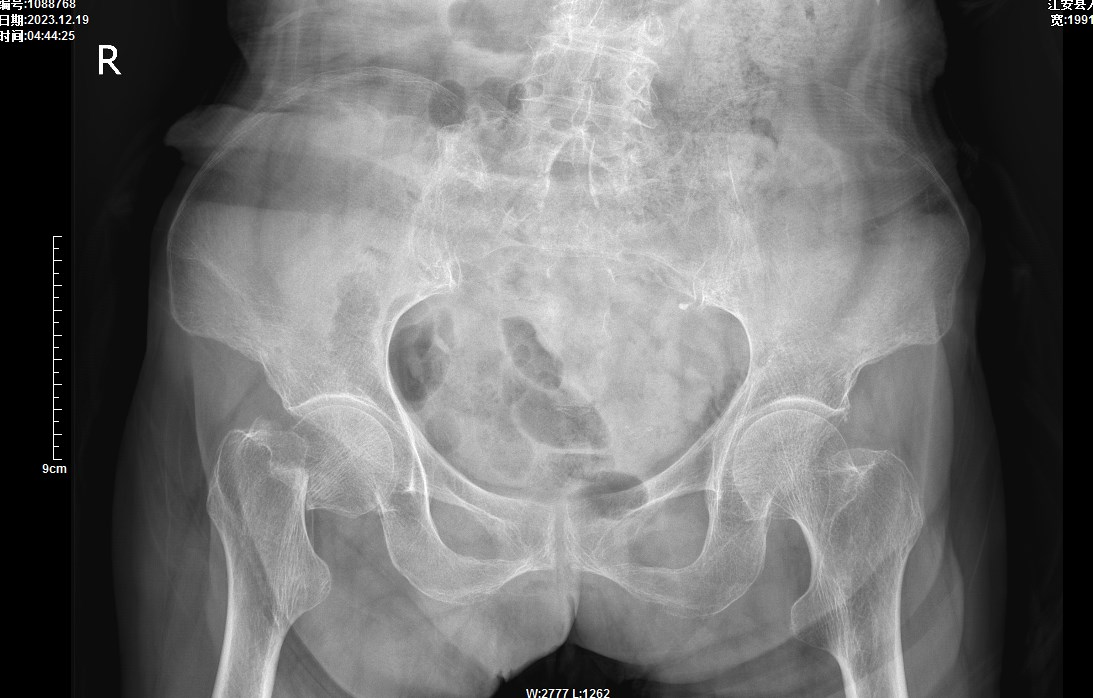

年已耄耋的李奶奶在家中走路时不慎摔伤,右髋部着地,致右髋部疼痛、活动受限,在完善影像学检查后诊断为:右股骨颈骨折。